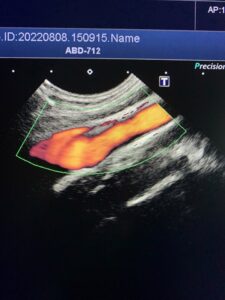

↑↑上の写真は、血管のようなチューブ状のものが見る方向によってどう見えるか?の例です。

←これが血管の横断面。

←そしてこれが同じ血管の縦断面。

同じ血管でも、断面によって見え方が全然違いますね!!

※わかりやすく、血管を赤く色づけしています。